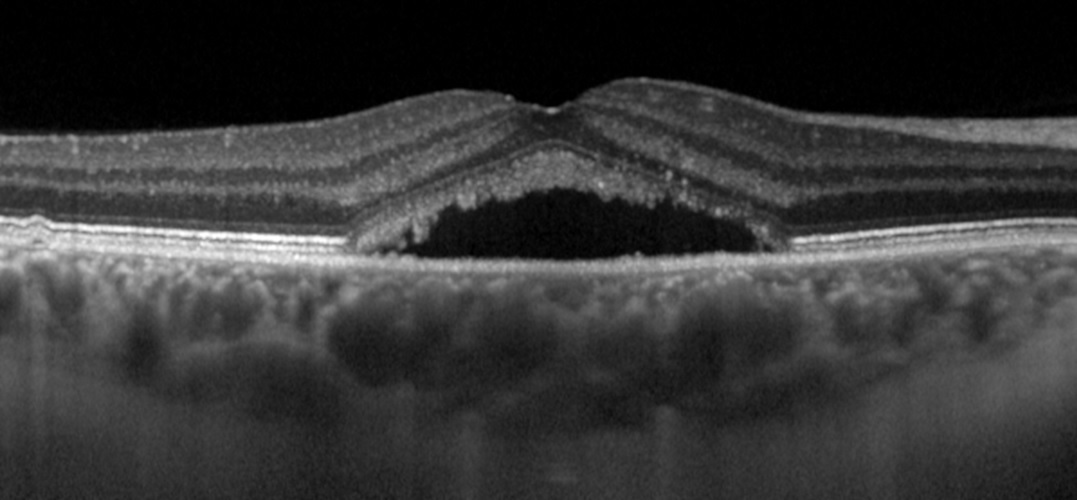

Retina muayenesi sırasında santral seröz retinopatiden şüphelenilirse göz arkası (fundus) fotoğrafı ve optik kohorens tomografi (OCT) çekilir. Optik koherens tomografi (OCT), gözün arkasını kaplayan ışığa duyarlı doku olan retinanın kesit resimlerini çekmek üzere ışık dalgalarının kullanıldığı girişimsel olmayan bir görüntüleme tekniğidir. OCT yoluyla retinanın her bir tabakası görülür ve tabakaların kalınlıkları haritalanıp ölçülür. Santral Seröz retinopatide retina altında veya retina pigment epitelinin altında sıvı biriktiği görülür.